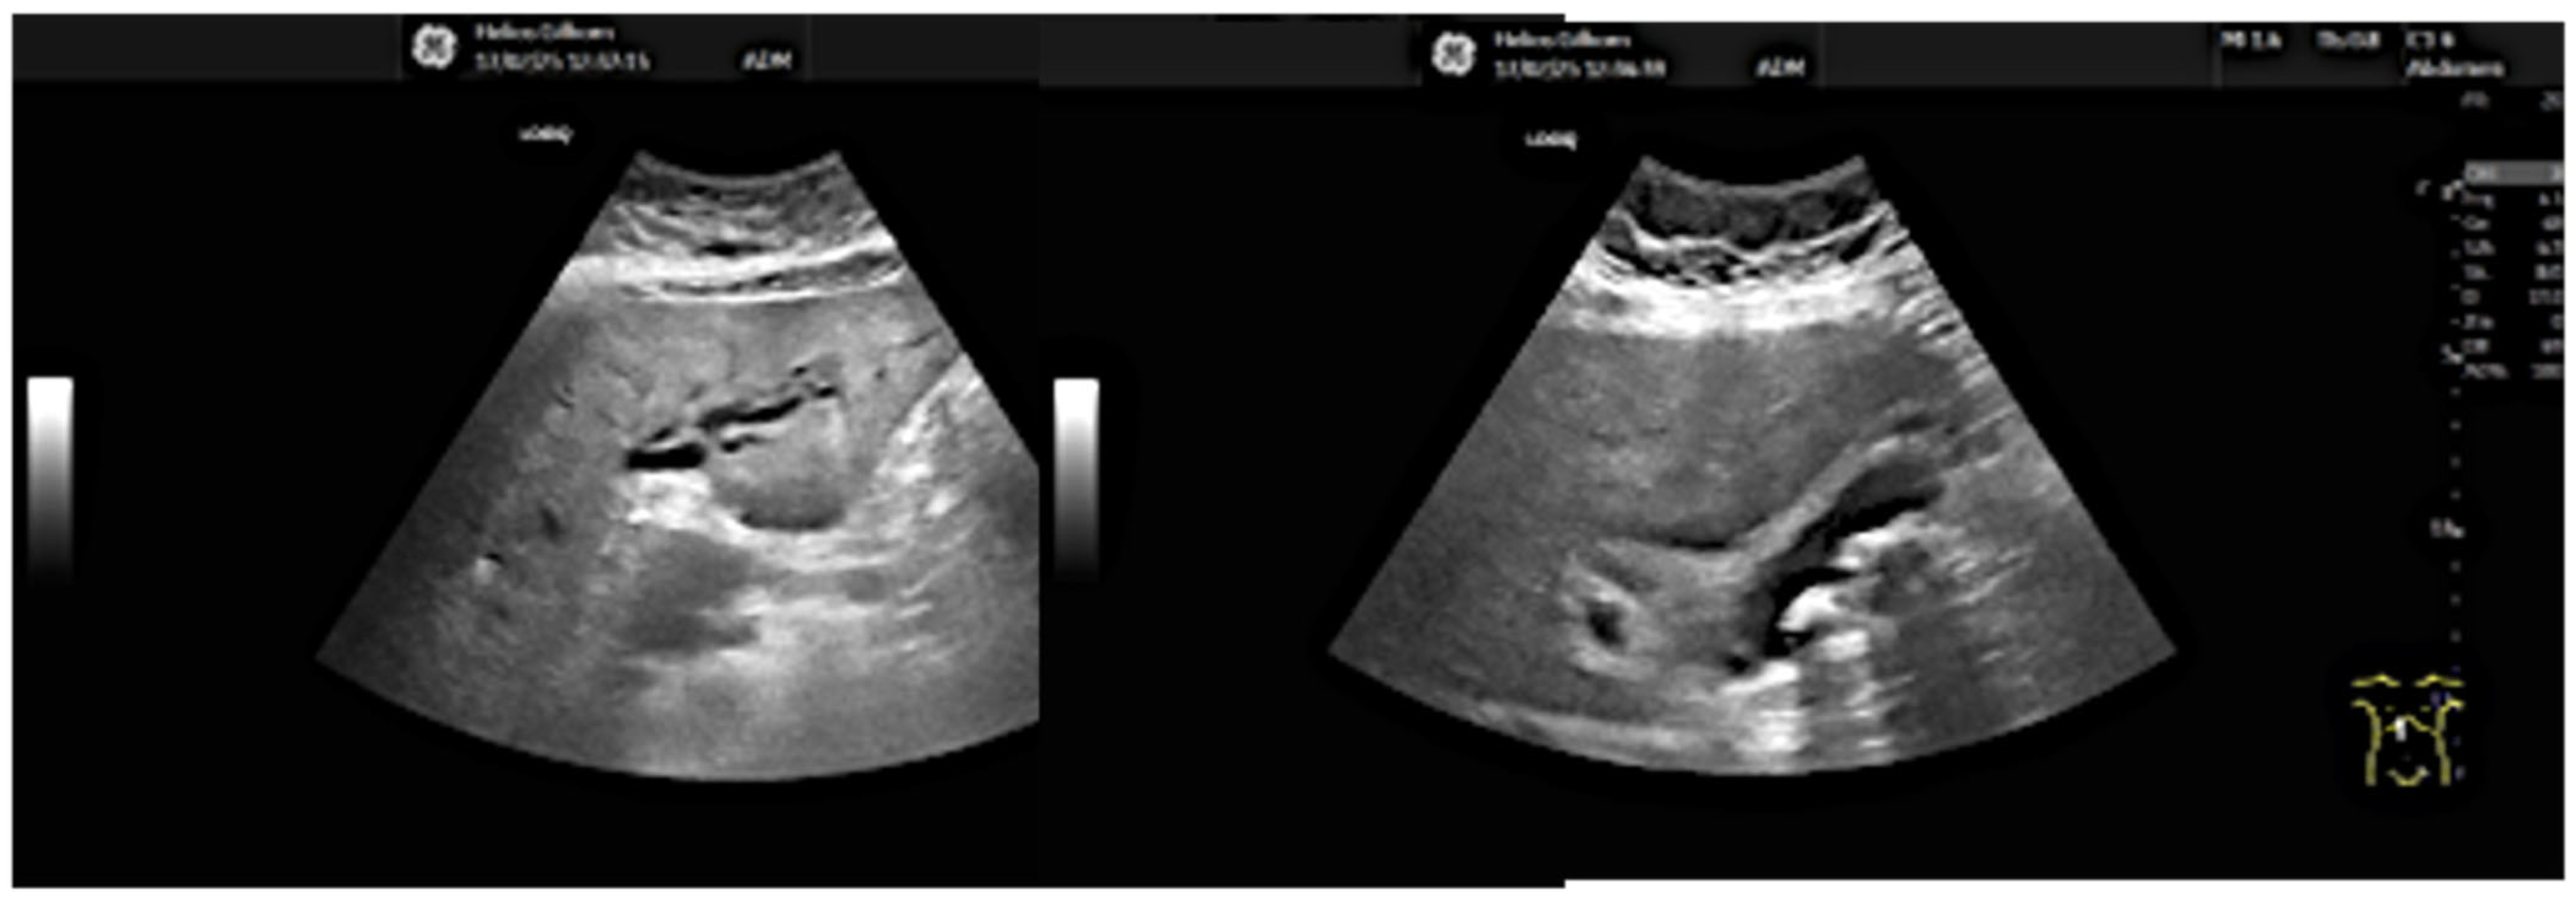

- 13.02: Abdominal ultrasound identified only gallbladder microlithiasis, without bile duct dilation (Figure 1).

- Repeat ultrasound revealed discrete hilar ductal dilation.